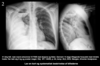

20

Q

Diagnose?

A

Venstresidig hæmothorax